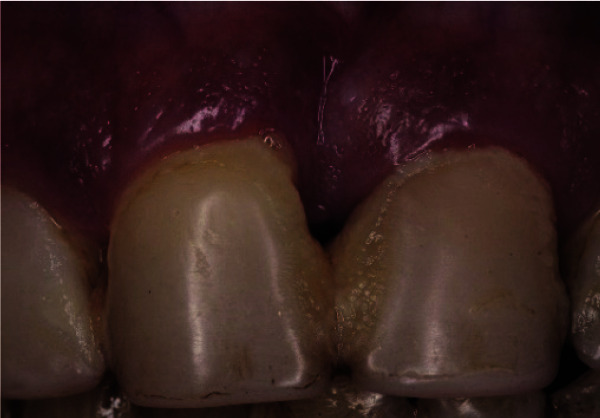

This case report exhibits a heavy smoker female patient with a localized stage III periodontitis who has been under the smoking cessation program during the pre-surgical period, followed by a strict maintenance program for the past twelve years, after being treated with guided tissue regeneration techniques and restored with zirconia prosthetic crowns. A 50-year-old, heavy smoker (> 40 cigarettes per day), systemically healthy female patient presented complaining of mobility and pain in the upper right central incisor, which was temporarily splinted to the left central incisor using resin composite. After clinical and radiographic examination, significant damage of the attachment apparatus, deep periodontal lesions extending the middle portion of the root, and severe infrabony defect were noted. Following the initial hygienic phase, a guided tissue regeneration surgery using xenograft bone substitute covered by a resorbable collagen membrane was performed. After six months of healing, four zirconia crowns were cemented on the central and lateral incisors based on patient esthetic compliance. During the 12-year follow-up period, neither residual pockets nor gingival recession were observed, and perfect marginal bone stability, and esthetic and functional results were noted. This case shows the predictability of a conservative surgical technique, the guided tissue regeneration, based on appropriate treatment planning and a strict maintenance program. It also demonstrates the importance of at least a 6-month healing period after such surgeries, allowing complete tissue maturation and a re-establishment of the supra osseous gingival tissues in order to locate the prosthetic margins without interfering with the soft tissues integrity.